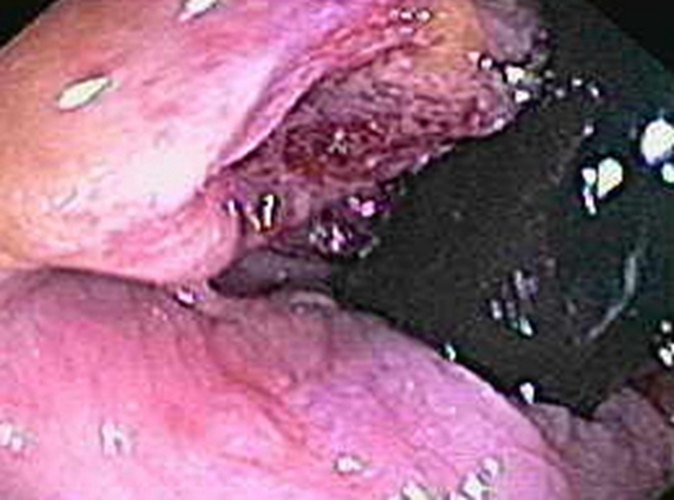

右半結腸癌圓形未分化癌常見 臨床 特點

右半結腸癌不規則形未分化癌常見 臨床 特點